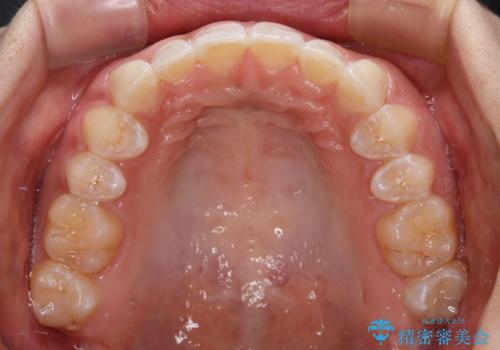

前歯のデコボコを治したい インビザライン矯正治療

- 前歯のデコボコ気になるとのことで来院された患者様です。

下顎骨が上顎骨に対して右側にシフトしており、さらに下顎が後方に位置しているため、非常に強い咬合力で食いしばっている状態でした。

上下顎ともに歯列全体の後方移動とIPR(歯と歯の間を削る)によってデコボコが解消するように設計し、インビザラインにより治療を行うこととしました。

上下正中位置は、治療開始時よりは改善したものの、ここが限界であろうというところでのゴールとなりました。